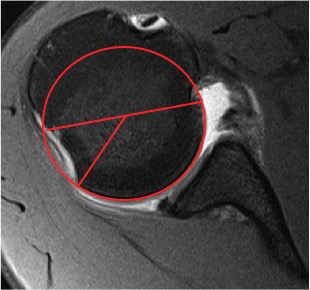

Best fit circle measurement

Best fit circle over inferior glenoid

- perpendicular line through center of circle

- measure percentage bone loss

10 - 15% defect

20 - 25% defect